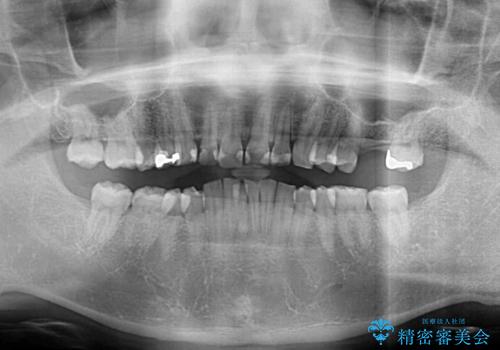

- 深い咬み合わせと前歯のデコボコ、奥歯の欠損を気にして来院された患者様です。

歯列矯正はインビザラインを使用し、矯正治療中の適切な時期に奥歯の欠損部位にインプラントを埋入することとしました。